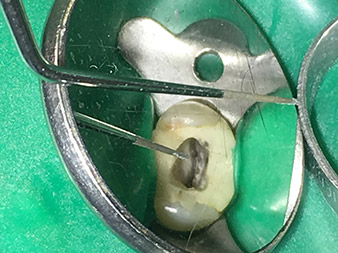

Preparazione atraumatica del pavimento della cavità con punta 4E.

La punta 4E è eccellente per la preparazione del pavimento della cavità in corrispondenza della transizione ai canali. Può essere usata in modo ottimale per arrotondare la transizione tra il canale e il pavimento della cavità in modo da produrre un foro che conduce nel canale. Inoltre lo strumento è la scelta ideale per rimuovere le eccedenze di dentina dai canali.

Nel complesso con questa punta la cavità può essere preparata in modo molto efficace e minimamente invasivo, arrotondando e smussando le eccedenze, gli angoli, i bordi.